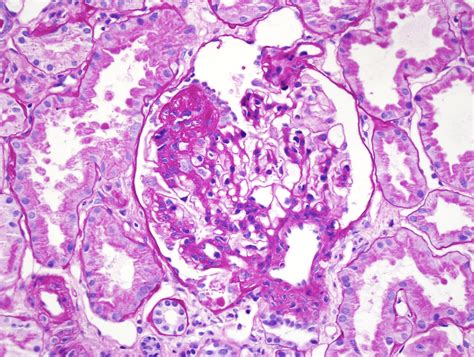

The term Focal Segmental Glomerular sclerosis describes a specific pattern of damage. "Focal" means that only some of the glomeruli are scarred, while "segmental" indicates that only a portion of each individual glomerulus is affected. Glomeruli are the tiny units in your kidneys responsible for filtering waste and excess fluids from your blood. When these units become scarred, they cannot function correctly, which may lead to the leakage of protein into the urine, a condition known as proteinuria.

Kidney Biopsy The gold standard to visualize scarring under a microscope.